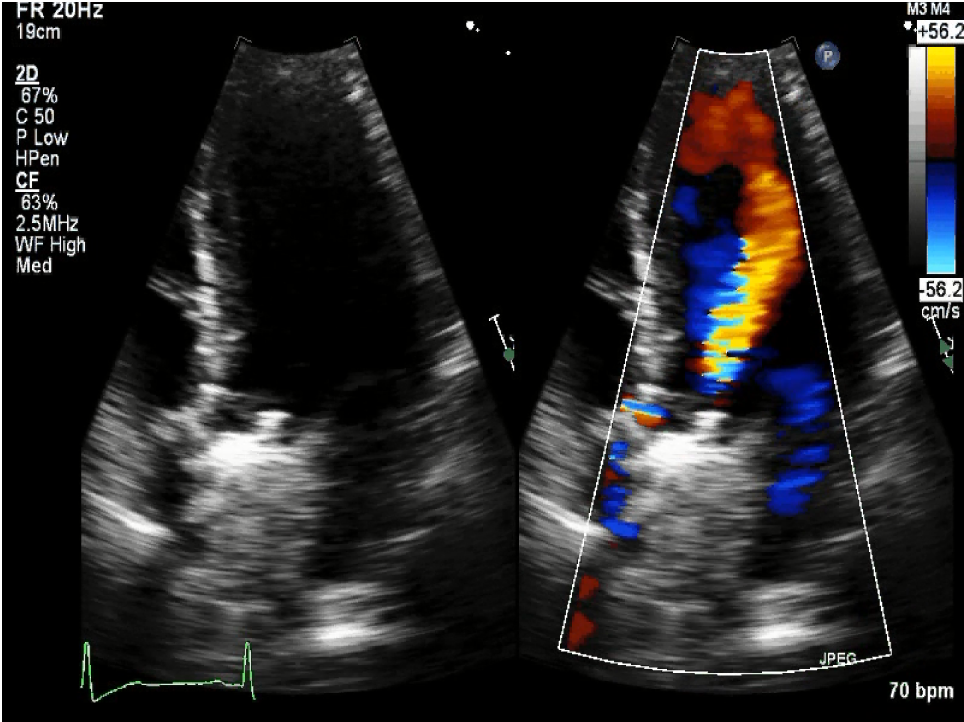

Doppler Echocardiographic Evaluation Of Prosthetic Valve Function | Heart

Doppler echocardiographic evaluation of prosthetic valve function | Heart heart.bmj.com

valve prosthetic heart figure doppler bmj